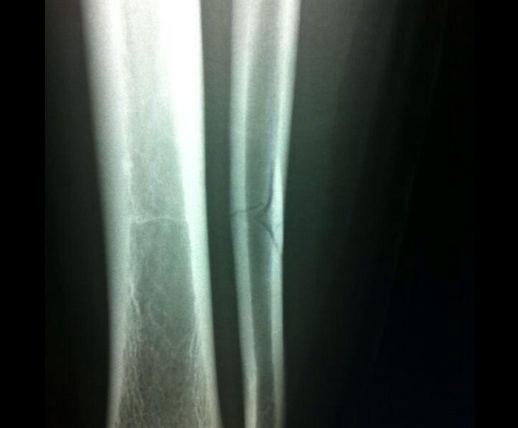

Photo : Bergessio partage sa fracture

L’ancien joueur de l’AS Saint-Etienne a subi une vilaine faute de Chiellini à la 76e qui ne lui a valu qu’un jaune. Après des examens, Gonzalo apprend la gravité de sa blessure. Résultat publié sur Twitter: une fracture du péroné et deux mois d’absence. Chiellini utilisera lui aussi le moyen d’expression préféré des footballeurs pour prononcer ses regrets: « Je voulais m’excuser envers Bergessio pour ma faute qui a causé sa blessure. J’étais sûr d’attraper le ballon, mais il avait anticipé, et malheureusement, j’ai frappé sa jambe. Je suis vraiment désolé et je lui souhaite un prompt rétablissement » .

Un carton jaune pour une fracture du péroné, ça fait surtout mal à l’arbitrage.